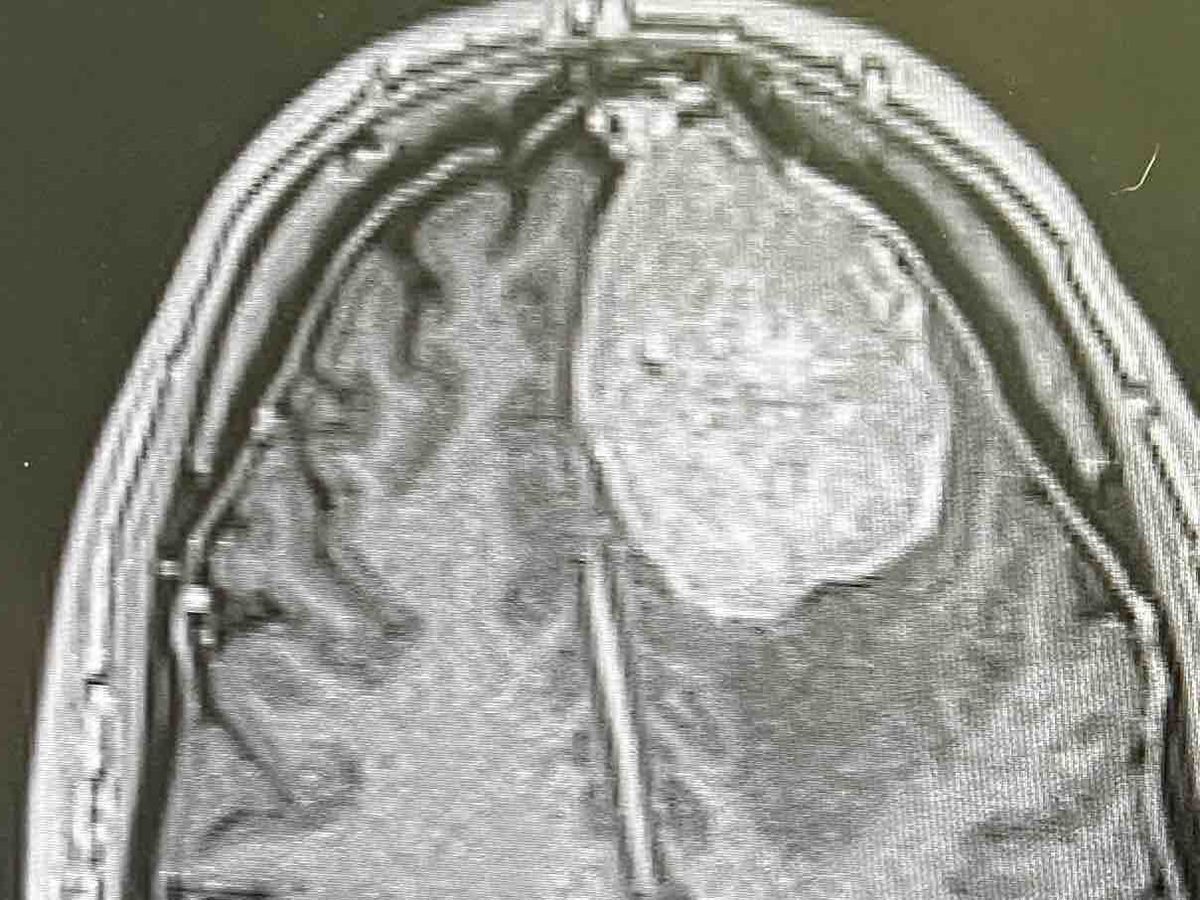

Once in the hospital I was given an MRI where

the neurological team fond a 5x4x4 cm tumor growing inside my left frontal lobe with current blood flow.

The pressure has been extensive and is around 15-20 years old according to the bruised aera and size on the scan.

The mass is not cosmetic or something that can be left untreated. It must have action taken now for my health. .

I have a tumor the size of a small lime to a tennis ball pressing on my left frontal lobe that must come out and I need some confidence it will come out.